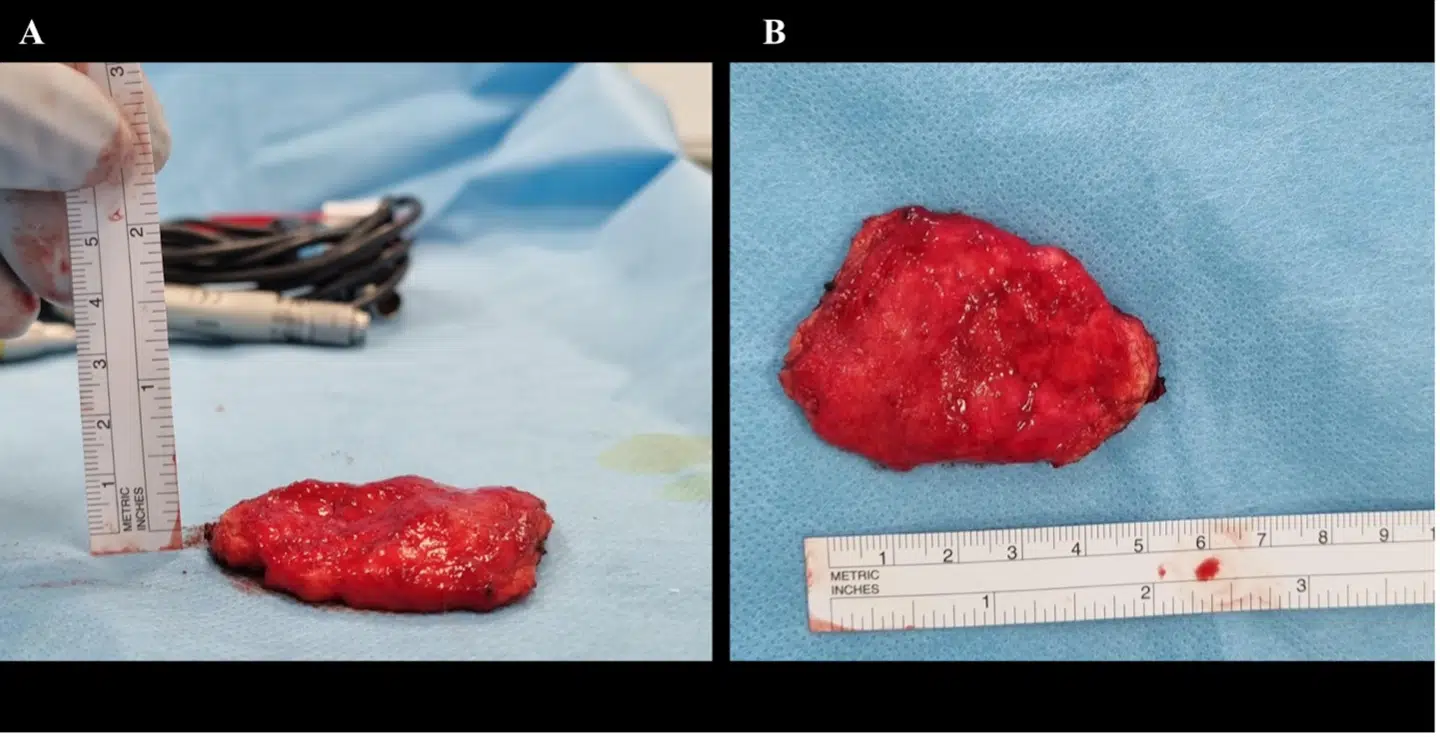

Sagen er, at lægerne blev opsøgt af den danske breakdancer, der var træt af en temmelig markant bule i sit hoved. Da lægerne scannede bulen, viste det sig at være en godartet svulst.

Bulen kaldes meget præcist for et ‘headspin hole’ eller en ‘breakdance bulge’. Første stadie i tilstanden er 'skaldethed, som følge af slitage', forklarer Christian Baastrup Søndergaard.

»Der sker det, når man laver headspins, at håret udtyndes. Det kan give en bar plet eller skaldethed. Men med tiden udvikler man en egentlig bule af arvæv under huden,« siger han.

Han forsikrer, at tilstanden ikke er farlig, men kan være en gene for patienterne. I det konkrete tilfælde lå svulsten uden på kraniet og har derfor ikke påvirket hjernefunktionen hos den mandlige hip hop danser.

Efter en times operationen på Rigshospitalets afdeling for hjerne og nervekirurgi blev bulen fjernet, og issen er i dag næsten så god som ny.